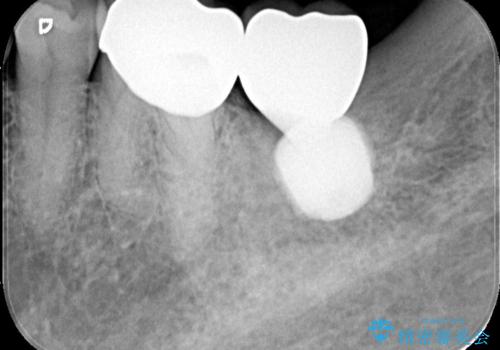

検査の結果、左下7番は歯周ポケットが8mmと深く、レントゲンでも根尖部から骨が溶けている状態が確認されました。エンドペリオ病変と診断し、精密根管治療による保存か、抜歯をしてインプラントで治療するかをご提案したところ、患者様は抜歯・インプラント治療を希望されました。

また、左下6番は銀歯と虫歯を除去した後、見た目や適合性に優れたオールセラミッククラウンで修復を行いました。

インプラントとセラミック治療を組み合わせることで、見た目も自然で噛み心地の良い状態を回復することができ、患者様にも大変ご満足いただけました。